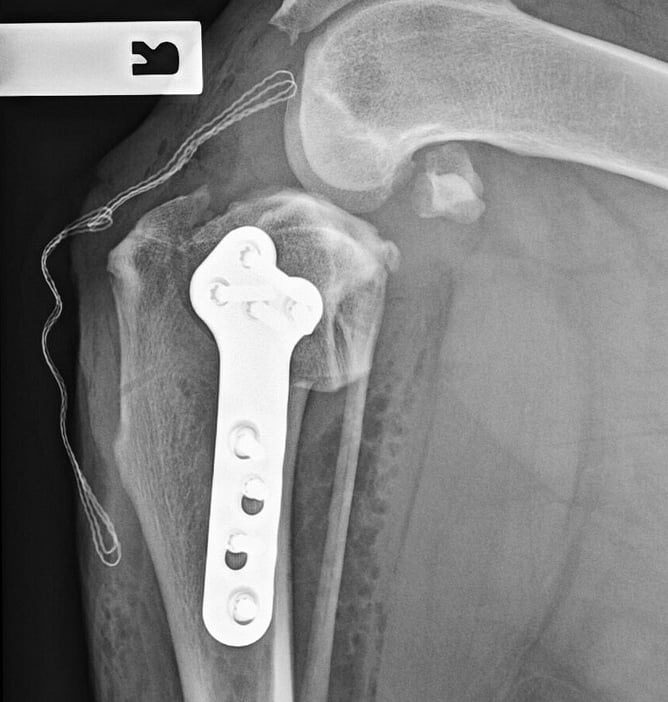

The TPLO involves cutting a curved osteotomy through the proximal tibia and rotating the tibial plateau segment to achieve a lower TPA (Lotsikas et al, 2013). After rotation, a plate and screws are applied to stabilise the osteotomised segment (Kowaleski et al, 2018). The aim is to neutralise cranial drawer by leveling the tibial surface so it is perpendicular to the load applied during weightbearing (Kowaleski et al, 2018). The TPLO alters biomechanics by placing additional reliance on the caudal cruciate ligament and muscular stabilisers of the stifle.

The TTA involves an osteotomy caudal to the tibial tuberosity and advancing of the tibial tuberosity so the patellar tendon is perpendicular to the tibial plateau. A titanium cage and plate hold the advanced portion of bone in place (Kowaleski et al, 2012). The TTA neutralises cranial drawer by altering forces through the stifle to be parallel to the patellar tendon, providing a biomechanical advantage to the quadriceps muscles (Guerrero et al, 2011). This procedure is less technically demanding, but has a higher incidence of post- operative patella tendonitis and meniscal tears compared with TPLO (Hurt et al, 2011).